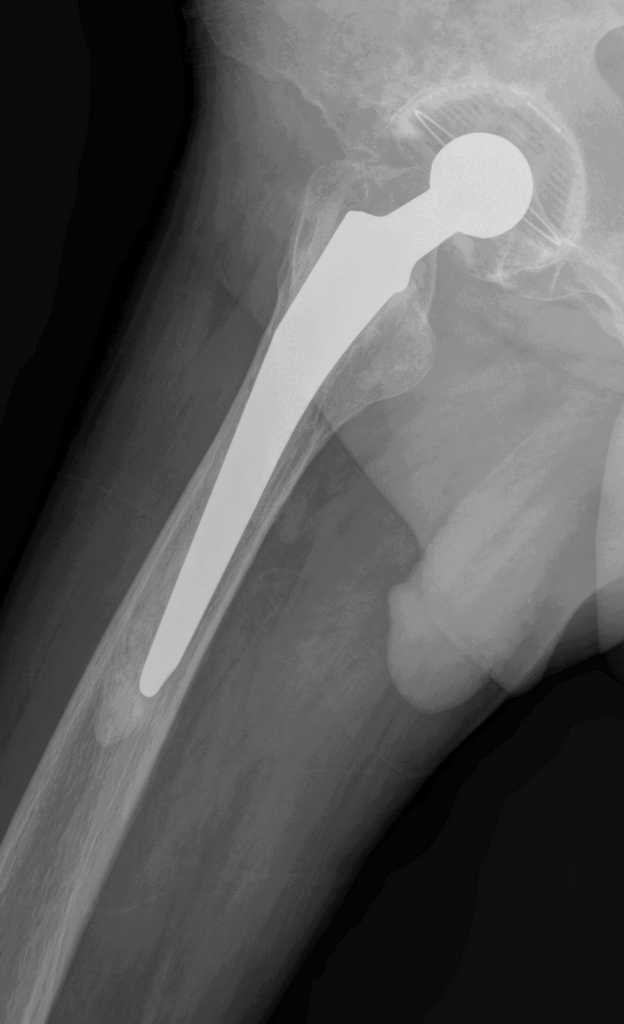

Больной М.,75л. Страдает коксартрозом. В 2005 справа и в 2007 г. слева эндопротезирование т\б суставов.

Через полгода после операции появилась боль в правой паховой области, правом бедре(средней и верхней третях)при движениях и особенно осевой нагрузке на правую ногу.

Евгений, справа ножка нестабильна, возможно она уже развернулась в мантии, да и вокруг чашки есть просветления. Видимо надо планировать повторное вмешательство с удалением ножки и цемента. Ножка должна удалиться легко, цемент в значительной своей части тоже. Сменить ножку лучше на бесцементную и не обязательно ревизионную, пойдет любая с элементами диафизарной фиксации. Состояние впадины оцените во время операции.

Признаки нестабильности ножки заметные, выраженная демаркация зоны кость - цемент. Нестабильность чашки сомнительная. Согласен, не обязательно применение ревизионной ножки, но фиксацию предпочел бы цементную. Данный метод фиксации уменьшает риск интраоперационного перелома бедра, упрощает и ускоряет период реабилитации пациентов пожилого возраста. Вероятно, желательно применить другой тип ножки, я бы использовал CS (CSL) -PLUS Plus Orthopedics, т.с."бюджетный" вариант. Может возникнуть проблема с удалением цементной "пробки".

Уважаемый Евгений, понятие стресс шилдинга не является синонимом нестабильности, хотя и является признаком неадекватности распределения нагрузки в системе "имплантат - кость" и может в последствие привести к "расшатыванию" эндопротеза.В данном случае на рентгенограмме правого тазобедренного сустава отчетливо видна сформированная "замыкательная пластинка" на внутреней поверхности кости (на границе с цементом). Причем, как раз в проксимальном отделе сегмента, то есть в зоне определяющей стабильность имплантатов типа Мюллер.

Болевой синдром в тазобедренном суставе при осевой нагрузке не характерен для корешкового с-ма или ишалгии. В данном случае, скорее всего мы наблюдаем "обратный" "с-м поршня". Когда изменение давления в костномозговом канале за счет перемещения нестабильной ножки (поршня)передается не в дистальные отделы бедра (классический "с-м поршня"), а за счет неподвижной (или малоподвижной) цементной пробки "отражается" в проксимальную часть, где и возникает боль. Возможно, конечно и наложение неврологическои и ортопедической симптоматики. Но, на мой взгляд, данные рентгенограммы дают достаточно информации о наличие проблем, по крайней мере, со стороны ножки эндопротеза правого тазобедренного сустава. А R-граммы, действительно хорошие... по качеству.